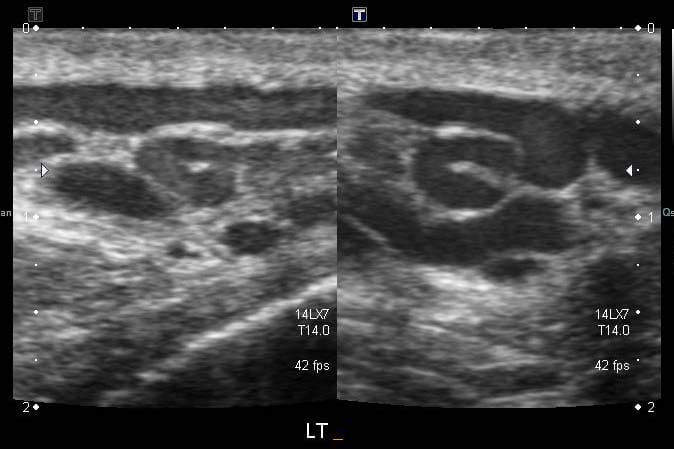

A varicocele is an abnormal swelling of the pampiniform plexus, the network of veins that drain blood from the testicles to the left renal vein and vena cava. The swelling is thought to be caused by the backflow of blood due to faulty valves further up the body, which causes blood to pool in these veins due to gravity. In rare cases, they can be caused by the compression of the left renal vein near the kidney.

Of course, testicular atrophy is detectable by an ultrasound, however most GPs will not refer for an ultrasound if a varicocele is diagnosed clinically, so there is usually no way to determine this. This reflects NICE guidance, that states diagnosis is usually clinical and only recommends (Doppler colour) ultrasounds in specific circumstances.